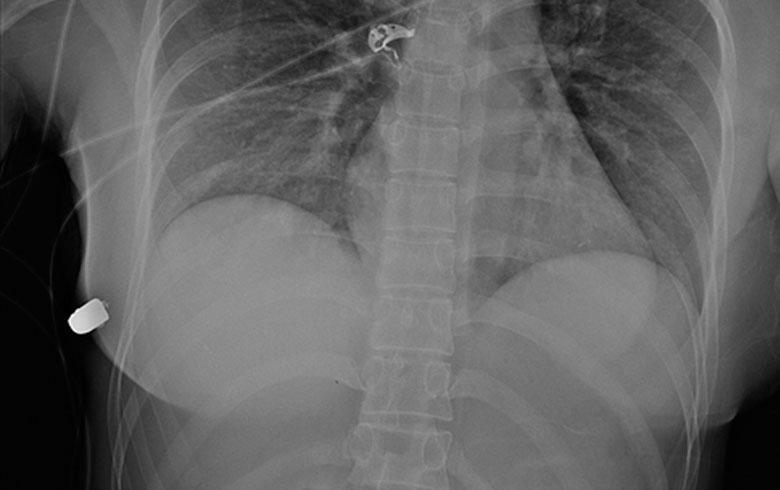

Las imágenes adjuntas al artículo médico dan cuenta de lo fundamental que fue la presencia de estos implantes, pues repelieron a la perfección el balazo.